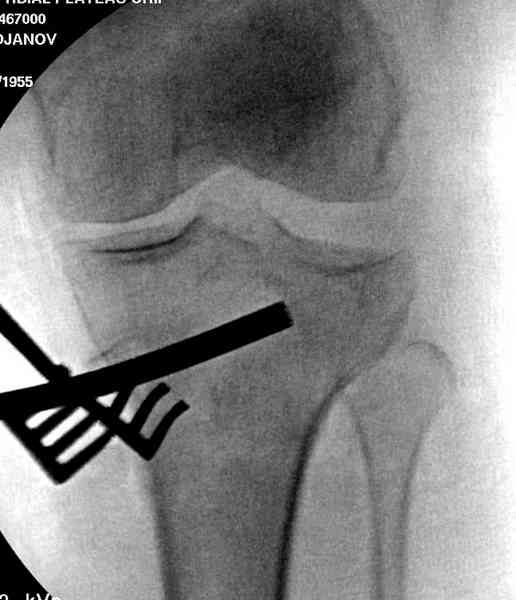

Из медиального окна можно приподнять латеральную

импрессию. Фиксация тремя параллельными шурупами в

эпифизарной части над импрессией. Создается крыша,

которая предупредит коллапс. На образовавшуюся полость - костная пластика из аутокости или синтетический заменитель. Мы применяем Osteoset в 4-5 мм диаметре таблеточки или иньекционную форму Prodens.

Медиально, обычно на протовоположной

строне, делается окно в кортикальном слое, кривым забойником под рентгеном поднимается импрессия.

После заполнения образовавшейся полости в метафизе

кортикальное окно можно прикрыть.

Это техника применяется, когда имеется

центральная импрессия, а при ипрессии с краевым переломом - после приподнимания импрессии опорная (Butress) пластина, как на снимке.